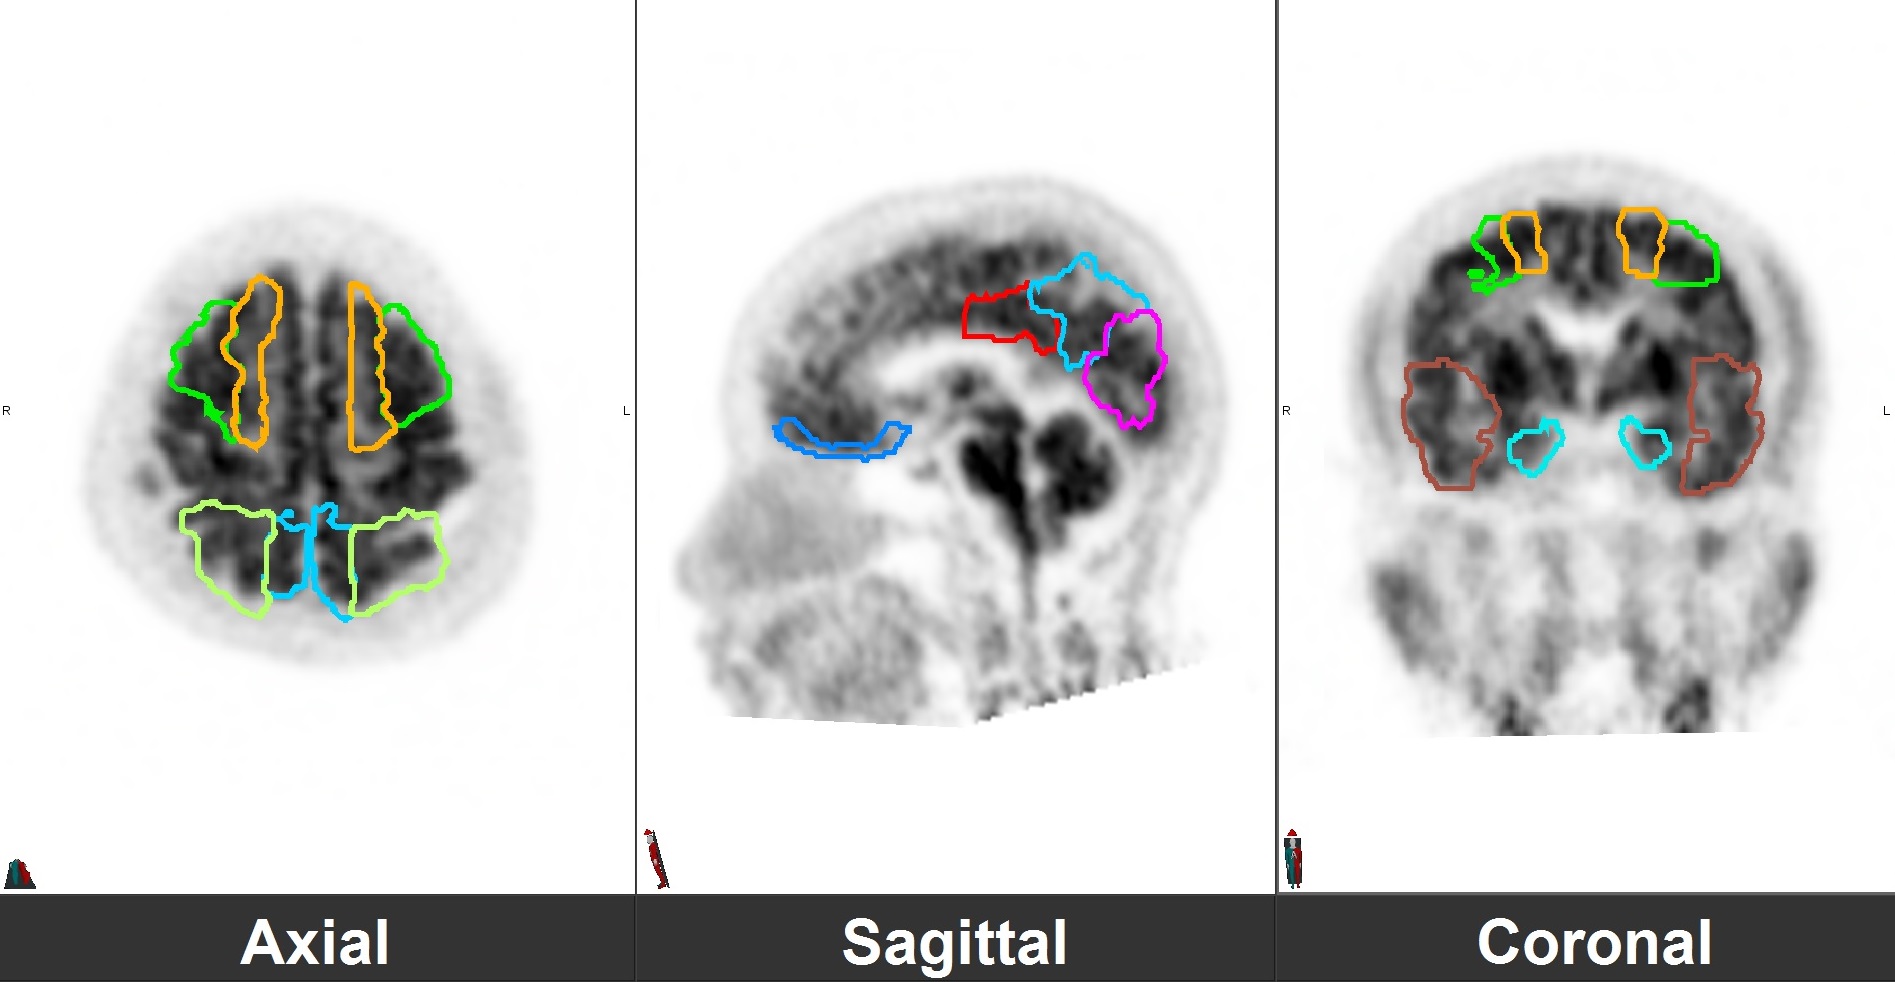

正电子/电脑双融扫描提供多项参数量化细胞活跃度,其临床应用范围很广,当中包括癌症丶心脏及脑神经疾病等。除最常应用的「标准摄取值 (SUV)」外,最新的应用包括利用影像数据作数学运算,然後得出更多独特的动态参数 (例如「Patlak Analysis」来计算绝对代谢率 (Absolute Metabolic Rate) )丶疗诊合一 (Theranostics) 及 体内外放射治疗规划中作病灶定位及剂量规划等,为诊断方法及治疗规划开创新模式。

运用多种针对不同类别癌细胞及疾病的正电子示踪剂及传统同位素示踪剂才是正电子扫描临床应用的独特之处。我们的放射性药物无菌制药室能生产多达16种利用标记氟18丶碳11或镓68合成的正电子示踪剂作临床使用。 常见的应用如下:

脑神经内分泌肿瘤

双示踪剂PET/CT (F-18 FDG及Ga-68 DOTATATE) 用於评估脑神经内分泌肿瘤体内的扩散情况